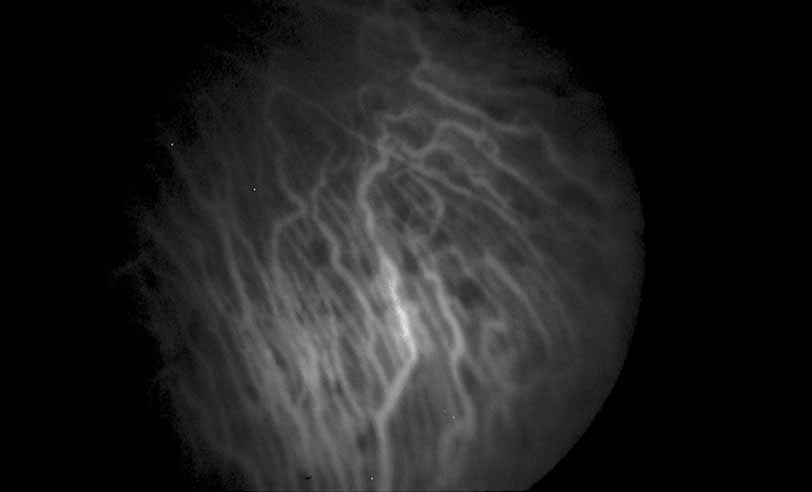

Fig. 12 Acute multifocal hemorrhagic retinal vasculitis. The patient later developed disk neovascularization with vitreous hemorrhage. Note the areas of neovascular leakage from the optic nerve.

Fig. 13 Acute multifocal hemorrhagic retinal vasculitis. The patient underwent scatter laser photocoagulation to the zones of retinal capillary nonperfusion, which resulted in regression of the neovascularization.